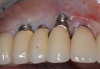

Fig 4. Skeletal growth can affect the esthetic zone at any age. A 35-year-old woman with a missing central incisor (No. 8) due to trauma was restored with an implant. Ten years later, as shown, a small discrepancy between the occlusal planes of the two central incisors due to continued skeletal growth can be noticed.

Figure 4

Further investigations of a crown's submersion risk among adults showed that significant skeletal dimensional changes as well as continuous eruption of teeth can occur later in life also (Figure 4).30 Such findings prompted researchers to follow-up single implant-supported prosthesis cases of different age populations for various time periods. Over an 8-year period, Thilander et al followed 15 adolescents who had single implant-supported crowns placed in the anterior maxilla.29 They reported no implant loss as well as an acceptable esthetic appearance in most subjects at the end of the observation period; however, eruption of the adjacent natural teeth continued and resulted in infraocclusion of the implant-supported crowns in some patients, as well as reduction of marginal bone level around some teeth adjacent to the implants. The authors specified that the infraocclusion was mainly found where incisor contact was absent meaning that good incisor stability is of utmost importance before an implant is placed in the esthetic area. Additionally, the authors tracked a single implant-supported crown placement in the upper incisor area of three adults and observed infraocclusion years after installation. They concluded that infraocclusion might occur in adulthood also and no chronological age is considered safe from such skeletal changes. In the adolescent group, the main vertical marginal difference occurred during the first 3 years of follow-up, which corresponded to the overall body growth of the individual. Still, infraocclusion further continued in 10 individuals during the subsequent years, despite body growth cessation. In a case report by Rossi and Andreasen, unfavorable clinical and radiographic findings were demonstrated over a 15-year period after a single tooth replacement by dental implants.25 In addition to the 9 mm discrepancy between the implant collar and the cementoenamel junction of the adjacent central incisor, the authors found that the maxilla significantly resorbed on the labial aspect during the skeletal facial vertical growth.

Based on clinical findings among young populations, it has been suggested that the most appropriate time for implant placement is the age when skeletal growth is finalized,31,32 which corresponds with the termination of general skeletal growth. However, the orthodontic literature has disclosed that facial growth actually continues throughout life (Figure 4),33 and therefore, at present, it is recognized that no decision as to the right time to place implants in the esthetic area is definite, and each case should be discussed with the patient and/or, in the case of adolescents, the parents as well.